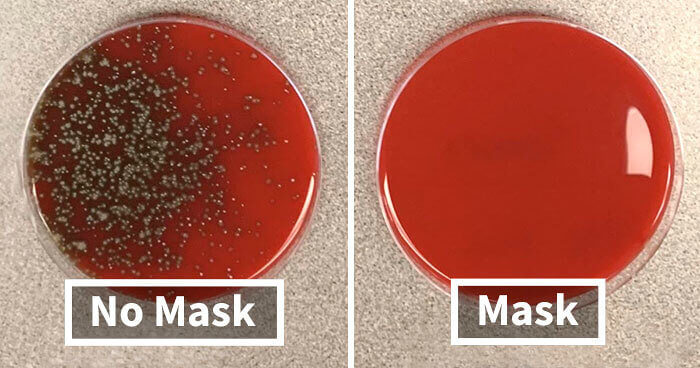

Check Out This Corona Test For Wearing A Mask Vs. Not Wearing One

There has been a great deal of controversy surrounding the use of face masks during the pandemic. Does paper really do anything to help stop the spread of disease and disaster? One scientist set out to prove that it does something in photos.

The research involved talking, sneezing, coughing, and singing over a petri dish with and without a mask. A day later, the bacteria grew only on one side. Were all viruses blocked, too? Tough to say from the photo. But it is interesting visually!